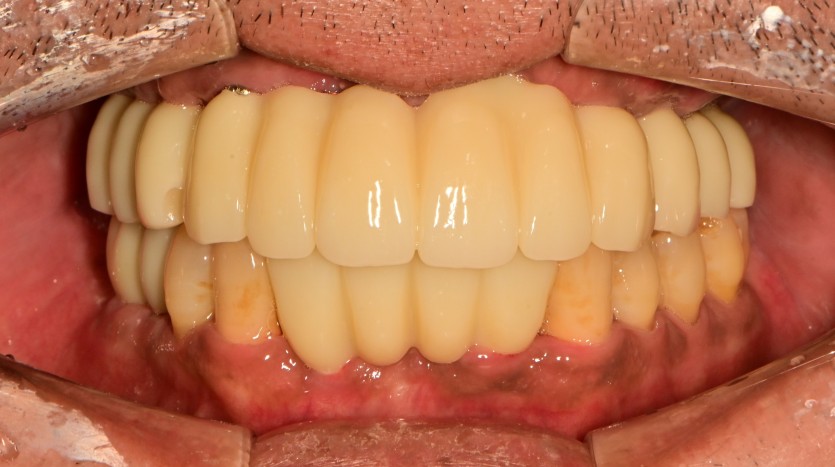

만 40세 상악 전체 임플란트 증례(하악 일부)

상악 전체 임플란트 증례입니다.(하악 일부)

14개의 임플란트로 완성하였습니다.